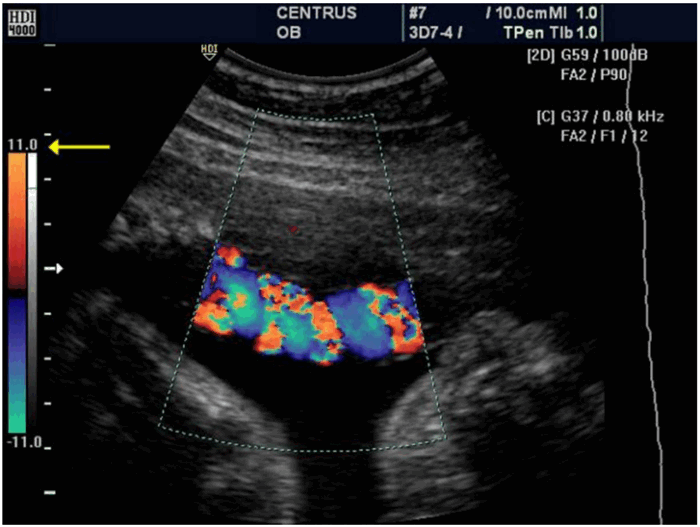

· Для визуализации Виллизиевого круга и проксимальной части средней мозговой артерии следует использовать режим ЦДК (рис. 5).

Рис. 5. Цветовое допплеровское картирование Виллизиевого круга.